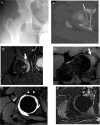

Atypical intra-articular osteoid osteoma can be difficult to diagnose and challenging to treat. We report a case of a right acetabular subchondral intra-articular osteoid osteoma in a young male patient which was initially diagnosed as femoroacetabular impingement due to its atypical clinical and radiological presentations. After fully working up the patient the lesion was successfully treated with percutaneous CT-guided low-power bipolar radiofrequency ablation using several per procedural articular cartilage thermal protective measures including intra-articular thermocouple, and continuous per procedural joint space cooling with Dextrose 5% solution. A precise RFA electrode placement, using the No-touch technique, and applying different passive and active thermal protective measures were helpful in avoiding collateral damage of the hip joint articular cartilages. atypical intra-articular osteoid osteomas necessitate pertinent correlation between the clinical and radiological presentations. As far as intra-articular or subchondral nidus ablation is concerned, thermal protective measures should be considered.